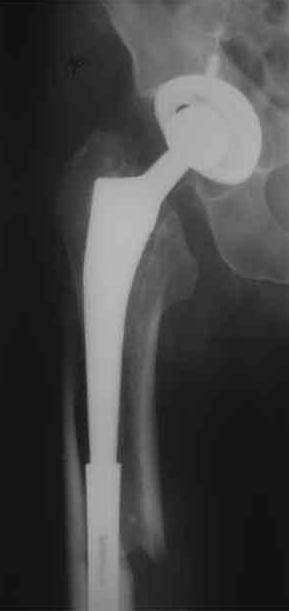

Уважаемые коллеги, продолжая дискуссию, начатую на "Вреденовских чтениях", хочу сказать, что принципиально сущестует два возможных варианта лечения.

1.Остеосинтез на ножке. Мне кажется, что применительно к этому случаю малоперспективный вариант. Синтез хорош, когда можно его выполнить в малоинвазивном исполнении и достигнуть стабильности. Действительно, если ножка б/цементной фиксации после этого не будет иметь фиксации, то ревизия не будет иметь проблем. В представленном случае стабильность синтеза сомнительная, а проведение доп.иммобилизации приведет к контрактуре суставов.

2. Применение ножки дистальной фиксации, мы отдаем предпочтение ножке Вагнера с фиксацией проксимального отдела на ножке. Более травматичное вмешательство, но при стабильной фиксации ножки реабилитация идет в обычном режиме.

Хочется показать два подобных случая, П-ка З. 72 лет и п-т Г. 80 лет. Сразу принимаю замечание, что это были ножки цементной фиксации, просто под руками не было бесцементника.

Пациента удалось осмотреть недавно. Достигнутый результат сохраняется. Перелом бедра сросся. Конечность опорная и безболезненная, ходит без трости. Ножка, похоже, реинтегрировалась, как и надеялись. Снимки и фото в приложении. Комментарии приветствуются.

Надо ли что-то делать дальше, как полагаете? Убрать винты? Убрать "удлинитель ножки"? Или оставить все, как есть? Спасибо заранее.